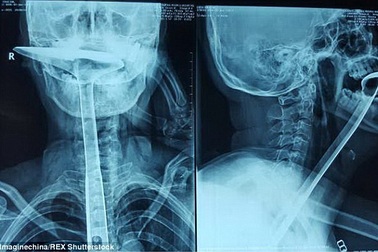

Suýt chết vì nuốt thìa để “thông” cổ họngMột phụ nữ Trung Quốc đã suýt bỏ mạng sau khi cho chiếc thìa nhà bếp dài 30cm vào họng để “thông” cổ họng.